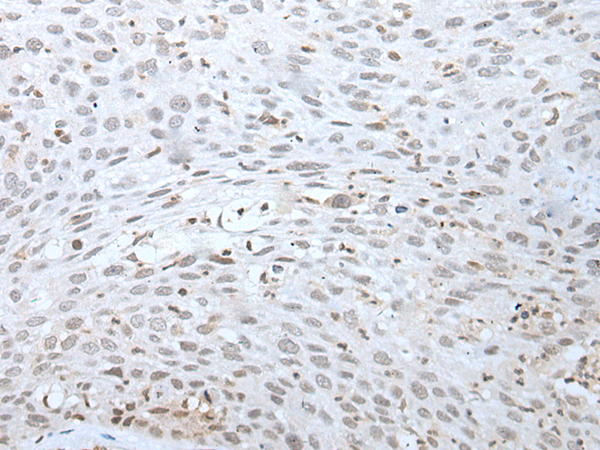

分类: 科研抗体货号: P12773别名:应用: WB反应种属: Human